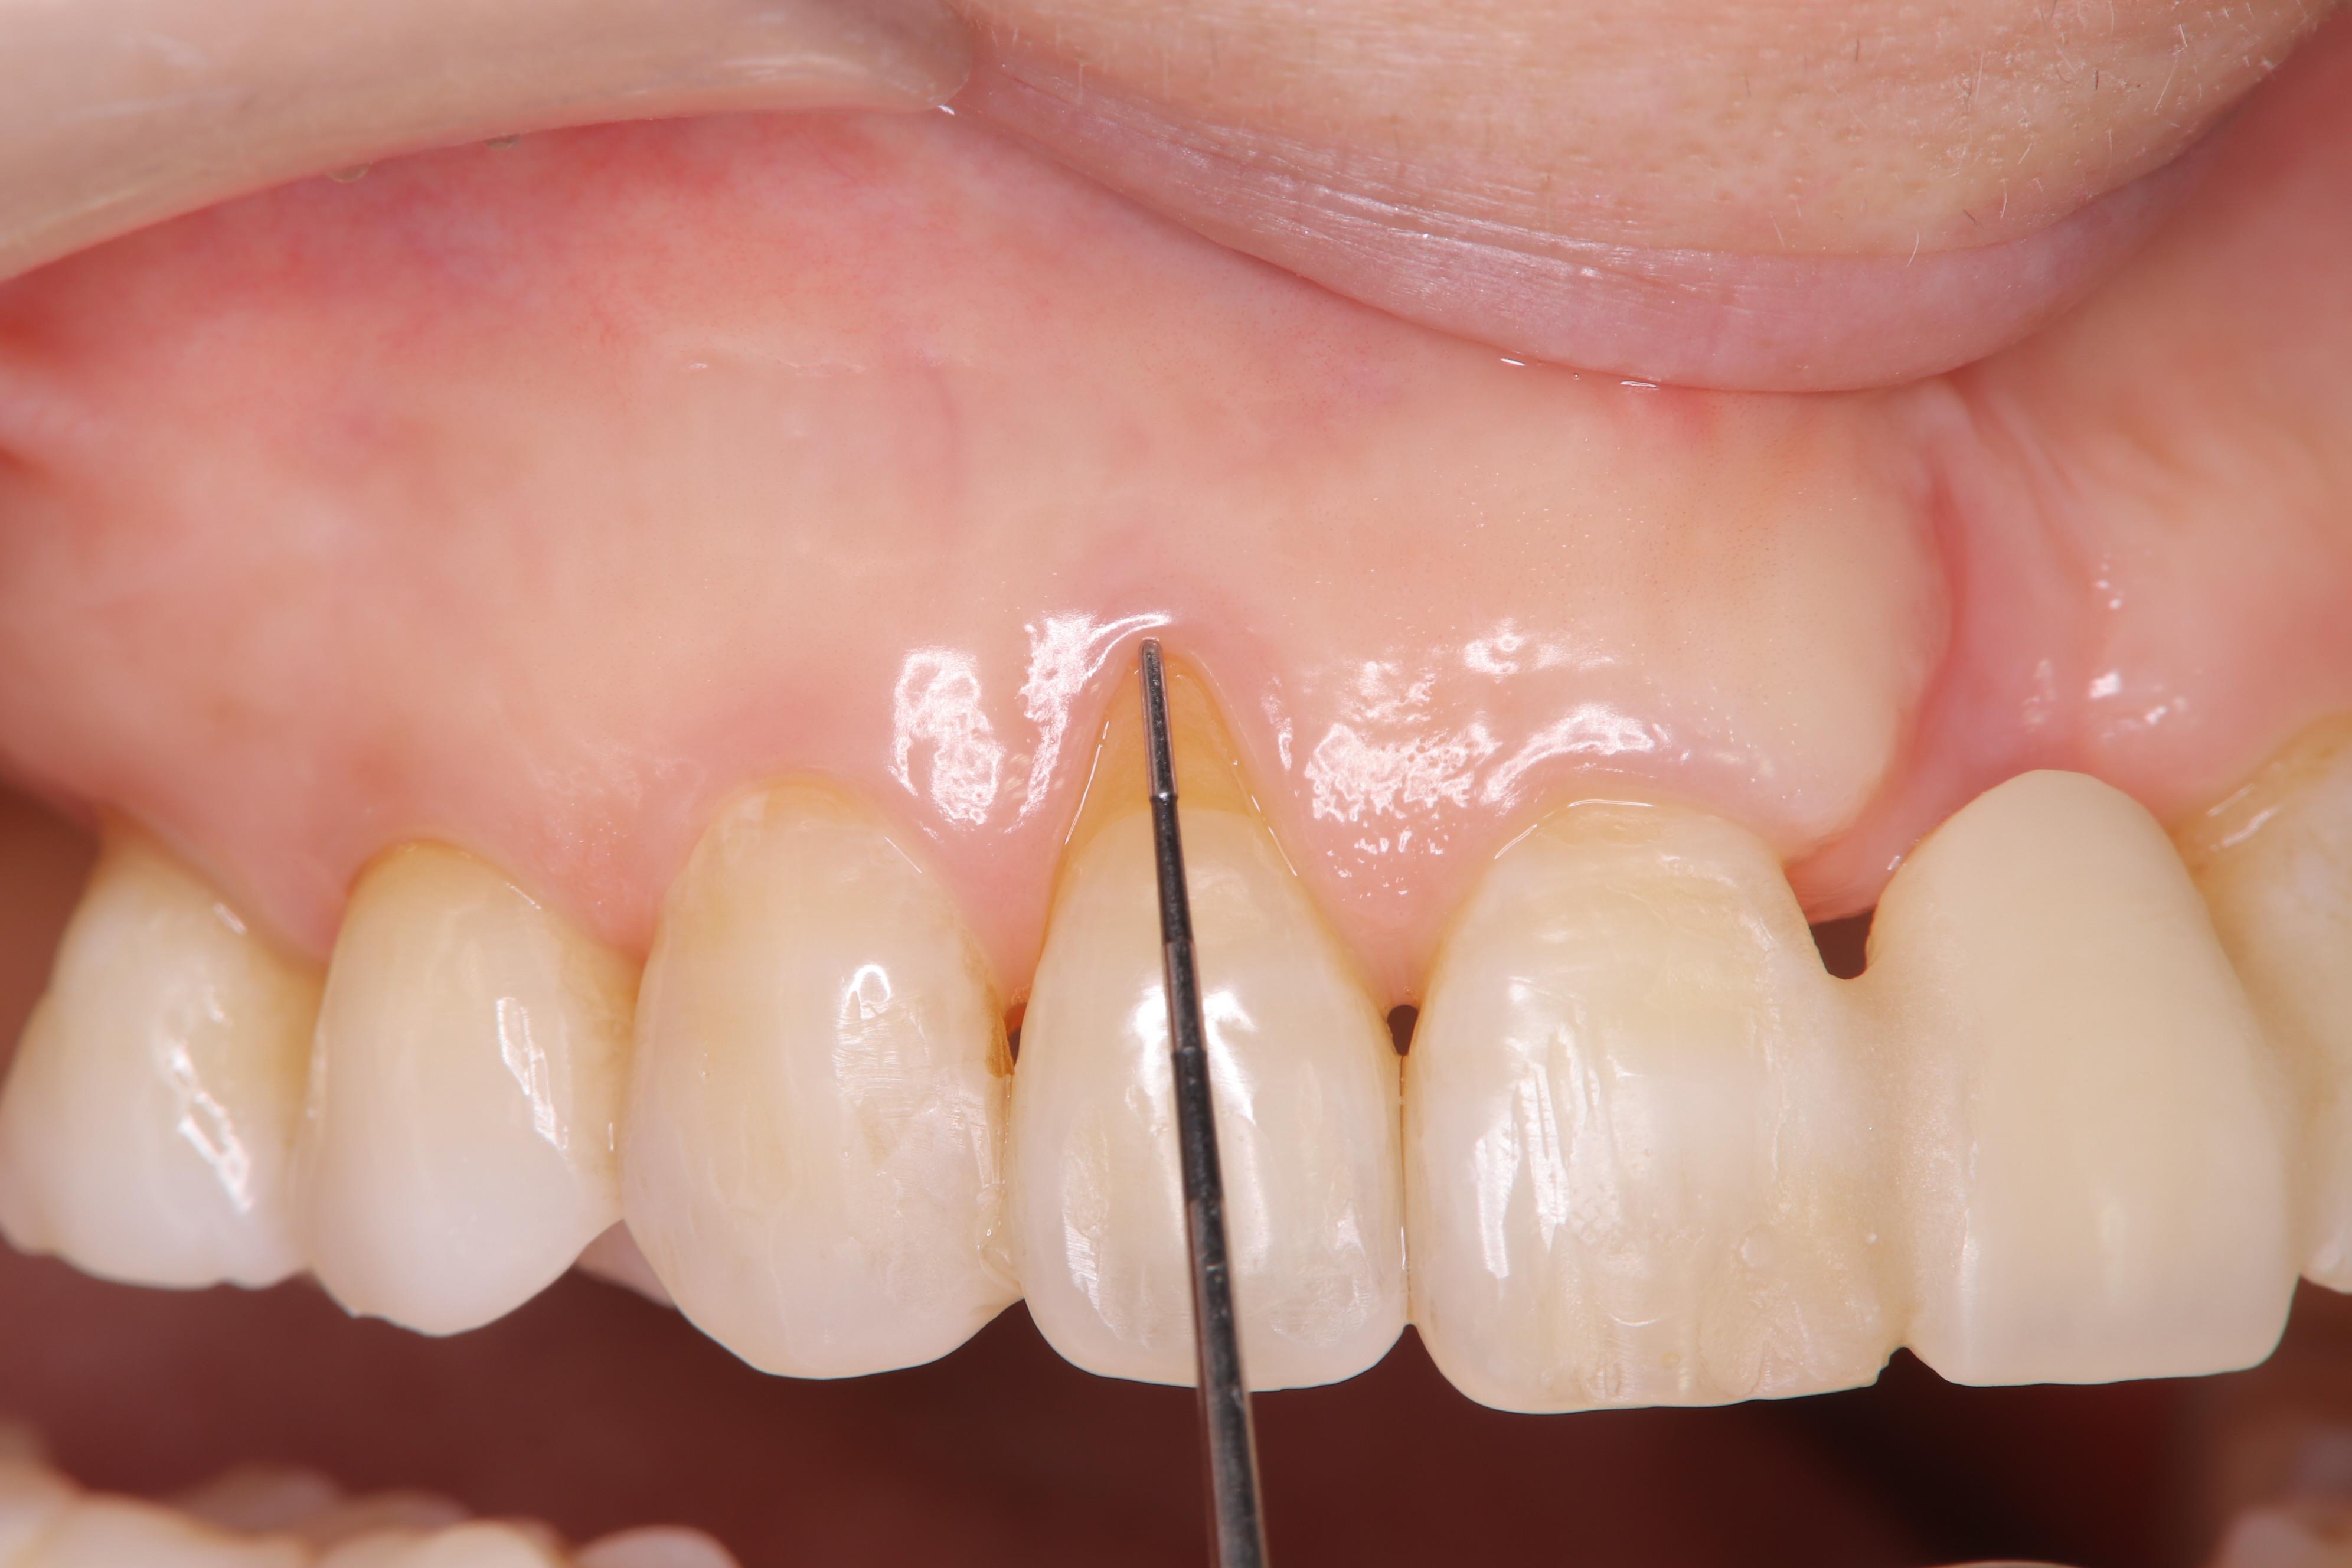

また、上顎右側の側切歯は、下の写真のように歯肉が下がり歯根が露出し、そこだけ歯が長く見えて気になるということでしたので、こちらも結合組織を移植して根面被覆を行いました。

下の写真は、結合組織移植後数ヵ月のものです。

歯肉の凹みや根面の露出が改善され、綺麗な歯冠・歯肉形態になりました。